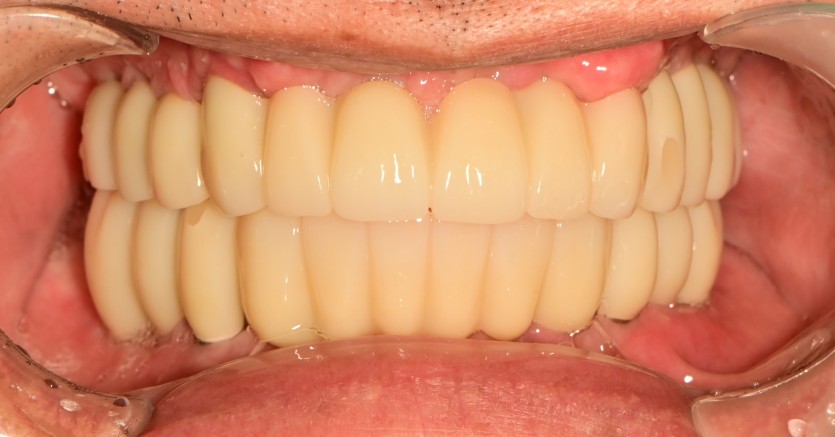

만 56세 전체 임플란트 증례

전체 임플란트 증례입니다.

18개의 임플란트로 완성하였습니다.